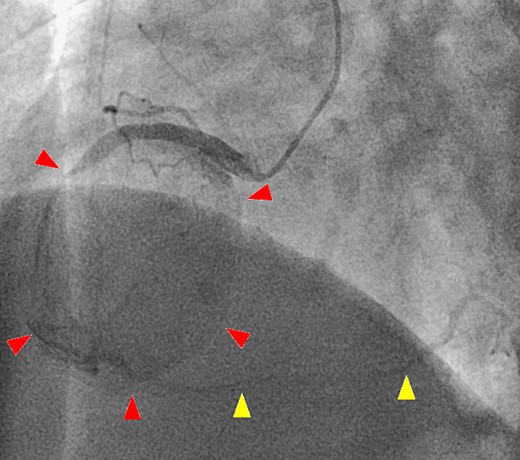

A 52-year-old man with transient ischemic attack was transferred to our hospital. He had a history of hypertension and dyslipidemia. He was conscious and had no particular symptoms after arriving at our hospital; however, an electrocardiogram showed ST-segment elevation in leads II, III, aVF, and V1–4. Enhanced computed tomography revealed a giant CAA at the RCA (Fig. 1). The aneurysm measured 50 mm in diameter and was completely occluded by a thrombus. Additionally, the coronary artery distal from the CAA did not show contrast. Emergency coronary angiography was performed. The RCA was occluded at segment #2 proximal to the CAA, and the CAA did not show contrast (Fig. 2A); however, the artery distal to the CAA showed contrast via a collateral artery from the left circumflex artery (Fig. 2B). Anticoagulation therapy involving intravenous heparin was started. After several hours, the ST-segment elevation disappeared quickly, and there were no particular symptoms. The creatine kinase level spiked to a maximum of 1475 IU/L, which then decreased to 432 IU/L on the next day. Four days after starting therapy, enhanced computed tomography and coronary angiography were performed again. They showed slight contrast in the CAA and the distal coronary artery (Fig. 3). Thus, surgery was performed to prevent the CAA from rupturing.

(A) Coronary angiography shows occlusion of the right coronary artery proximal to the aneurysm (arrow). (B) The artery distal to the aneurysm shows contrast via a collateral artery from the left circumflex artery (arrow).